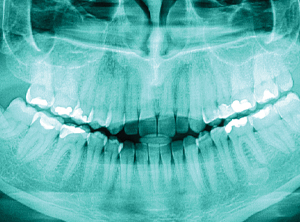

3D x-ray image capture

Using advanced imaging systems, our dentists can capture detailed 3D x-ray images of your dental anatomy. This high-resolution imaging helps support clinicians in accurately diagnosing anomalies and creating individual tailored treatment plans.